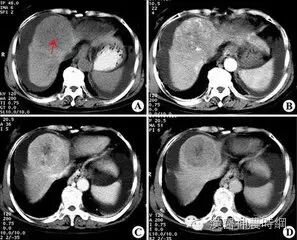

2.计算机X线体层扫描(CT)  CT是一种安全、无创伤、高分辨力的检查方法。对肝癌的定位诊断很有价值。CT能显示肿瘤的大小、位置、数目及与周围脏器和大血管的关系,可检出1cm左右的早期肝癌。并有助于了解是否伴发肝外转移,如肝门淋巴结,胰头后淋巴结等。结合增强扫描可以判断病变的性质,对肝癌与肝血管瘤的鉴别有较大的价值。平扫下肝癌多为低密度占位,边缘清晰或模糊,部分有包膜的肝癌可显示晕圈征。较大的肝癌可见更低密度的坏死区,少数肝癌可见钙化。增强扫描有滴注法、大剂量推注、推注加动态扫描等。肝癌在动脉期尤以注药20s内强化最为明显,癌灶密度高于周围肝组织。30~40s后造影剂进入细胞间隙转入实质期,病灶又恢复为低密度,显示更为清晰。近将肝动脉造影与CT检查相结合,开展CT动脉造影(CTA)和CT动脉门脉造影(CTAP),对提高小肝癌的检出率有一定价值。也有人在CT检查前一周经肝动脉插管注入碘化油(lipiodo1),再做CT扫描,这种lipiodol-CT可检出0.5cm的小肝癌。对于<1cm的肝癌,Uchida报告US、CT、肝动脉造影和几种CT检查的分辨力为:US 63%、普通CT 12%、滴注法增强扫描65%、CTA 71%、CTAP 80%、lipiodol-CT 89%。

3.磁共振显像(MRI)  MRI在肝癌诊断中的作用日益受到重视,其诊断价值有超过CT的趋势。与CT相比其优点为:无电离辐射,能获得横断面、冠状面、矢状面3种图像,对肿瘤与肝内血管的关系显示更佳;对软组织的分辨力高;对肝癌与肝血管瘤、囊肿及局灶性结节性增生等良性病变的鉴别价值优于CT。国外报道MRI对大于2cm的肝癌的检出率为97.5%,小于2cm者为33.3%,检出最小的肝癌为1.5cm。近年有采用钆离子螯合剂作对比增强剂成像,提高了MRI对微小病灶的检出率,并有助于肿瘤性质的判断。原发性肝癌在T1加权像上多为低信号占位,少数可为等信号或高信号,坏死液化信号更低;伴有出血或脂肪变性则局部呈高信号区;钙化表现为低信号。在T2加权像上,绝大多数肝癌表现为强度不均的高信号区,少数可呈等信号区;液化坏死区信号强度很高;钙化则为点状低信号。门静脉或肝静脉癌栓在T1加权和质子密度像上呈稍高的信号;在T2加权像上为较低的信号强度。假包膜在T1加权像表现为肿瘤周围的低信号带,在T2加权像上内层纤维组织为低信号带,外层丰富的受压的小血管或胆管则为高信号带。MRI T1加权像可显示清晰的肝脏血管解剖,对指导手术有很大的参考价值。